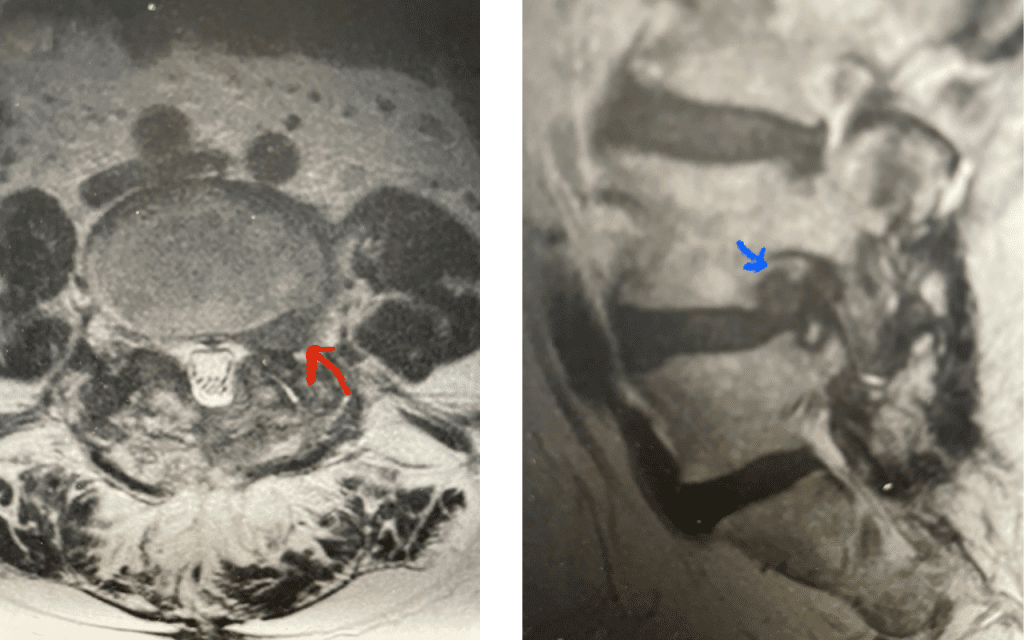

Fig 4: Axial and Sagittal T2-weighted lumbar MRI demonstrating a left lateral foraminal disc herniation (red arrow) causing compression of the exiting L1 nerve root against the undersurface of the pedicle of L1.